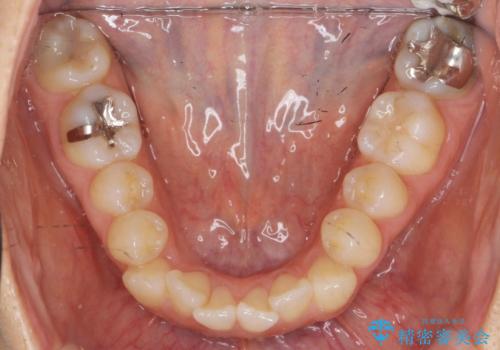

- 気になる前歯のガタつきをマウスピースで治療したいと希望され来院されました。

当日に矯正検査を行い、骨格・歯に問題がないことを確認しマウスピースによる矯正治療を進めます。

IPRを前歯部に少量行うことで、非抜歯でも前歯が外に飛び出さない仕上がりを達成できました。